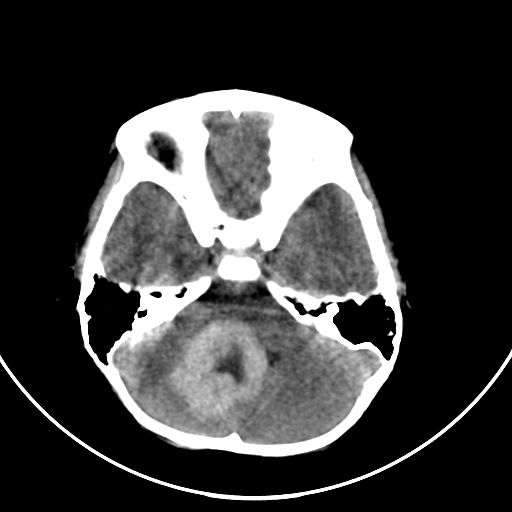

以下是引用zjzjr在2008-7-27 9:56:00的发言:[br]考虑髓母细胞瘤伴梗阻性脑积水.建议增强或mri

以下是引用子十在2008-7-27 9:53:00的发言:[br]考虑髓母细胞瘤